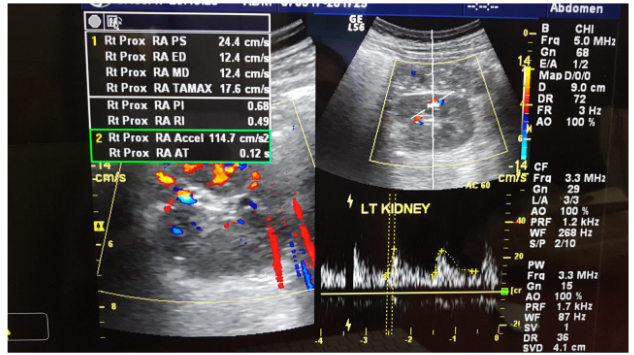

Urine test did not show albuminuria, while renal function deteriorated in the last six months: urea was increased from 25 to 49mg/dl and creatinine from 0.7mg/dl to 1.3mg /dl. In kidney ultrasound the right kidney was at 11cm while the left kidney was smaller, at 9.5cm. The triplex of the renal arteries showed a significant degree of stenosis in the left renal artery (Figures 1 & 2). The maximum velocity in doppler must not exceed 1.4 m/s while our patient has 5m/s in the left artery! Additional pathological findings are: (Figure 3)

Figure  3 Resistance index and acceleration time of left renal artery.

Resistance index 0.49 (RI:0.6-0.7), is a general indicator of renal parenchymal disease. In patients with severe renal artery stenosis >75-80%, in the early stages of the disease the resistance index is low (RI<0.6). Is attributed to marked vasodilation promoted by self-regulating endothelial mechanisms and aimed at protecting the ischemic kidney. As the disease develops and affects the renal parenchyma, the vascular resistance increases and consequently increase RI>0.8. The resistance index has not only diagnostic but also predictive value: RI>0.8 indicates severe parenchymal disease and is an unfavorable indicator of renal function repair and correction of arterial hypertension after reperfusion.

The acceleration time 0,12s (AT:<0,07sec), indicative renal low flow. The patient was then subjected to magnetic angiography of renal arteries (MRA) confirming the triplex’s findings: 90% stenosis of left renal artery immediately after the outgrowth of the abdominal aorta (Figure 4). In the radioactive nephrogram, impaired left kidney function is demonstrated at 36% in the relative involvement of total renal function (split function), as opposed to the right kidney that contributes to 64% of glomerular function (Figure 5). In the same test was calculated with gates technique the GFR in the right kidney at 76.2ml/min/1,73m2,while in the left kidney 26.6ml/min/1,73m2.